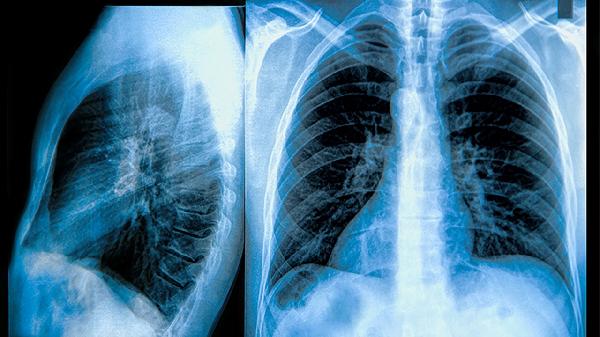

長期暴露于霧霾、工業(yè)廢氣等污染環(huán)境會導(dǎo)致顆粒物在肺部積聚。外出時可佩戴符合國家標準的防護口罩,室內(nèi)使用空氣凈化設(shè)備。職業(yè)暴露人群需嚴格做好防塵措施,定期進行肺功能檢查。